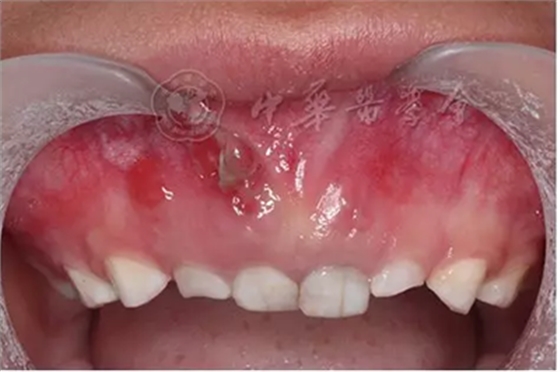

(1)疾病定義及口腔表現(xiàn):中性粒細胞減少是由于外周血中粒細胞的絕對值減少而出現(xiàn)的一組綜合征。出生后2周至1歲的嬰幼兒中性粒細胞低于1×109/L、1歲以上兒童中性粒細胞低于1.5×109/L時,即可診斷為中性粒細胞減少癥。當中性粒細胞低于0.5×109/L時則可診斷為粒細胞缺乏(agranulocytosis)。根據(jù)中性粒細胞減少的程度和持續(xù)時間,病情的輕重不同。病程初期為發(fā)熱,之后表現(xiàn)為反復感染且難以控制,好發(fā)于呼吸道、泌尿系、皮膚和黏膜等。在口腔主要表現(xiàn)為反復發(fā)作的口腔炎、口腔潰瘍,牙齒松動、乳牙早失,牙齦紅腫、糜爛、齦袋溢膿及牙槽骨喪失等(圖1)。

圖1 4歲中性粒細胞減少患兒乳牙牙齦明顯紅腫、糜爛